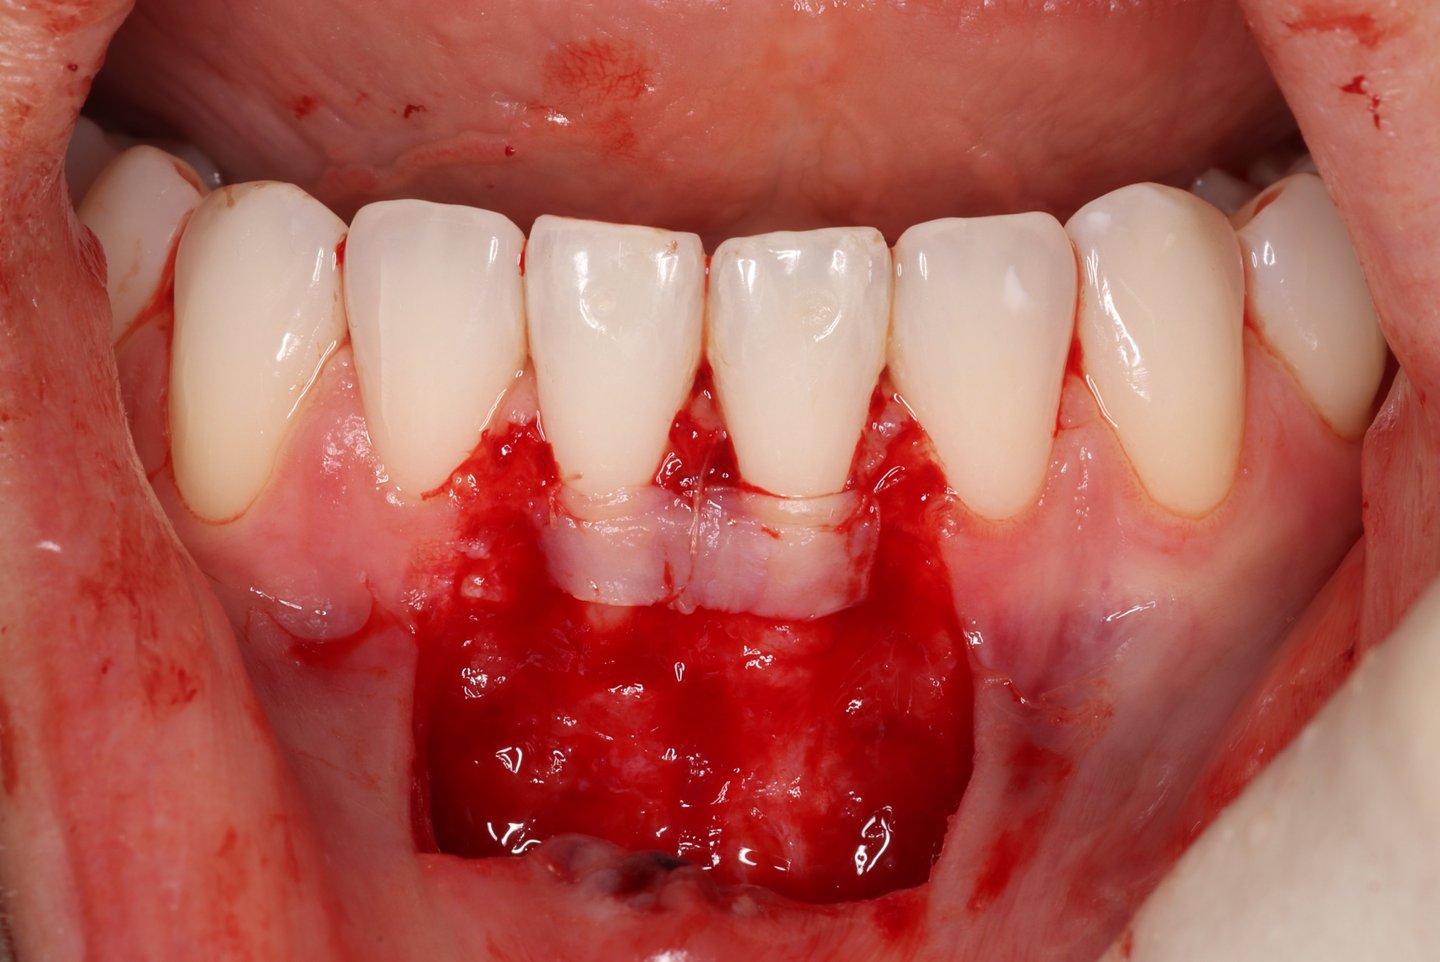

Chirurgie muco-gingivale

Traitement des récessions gingivales